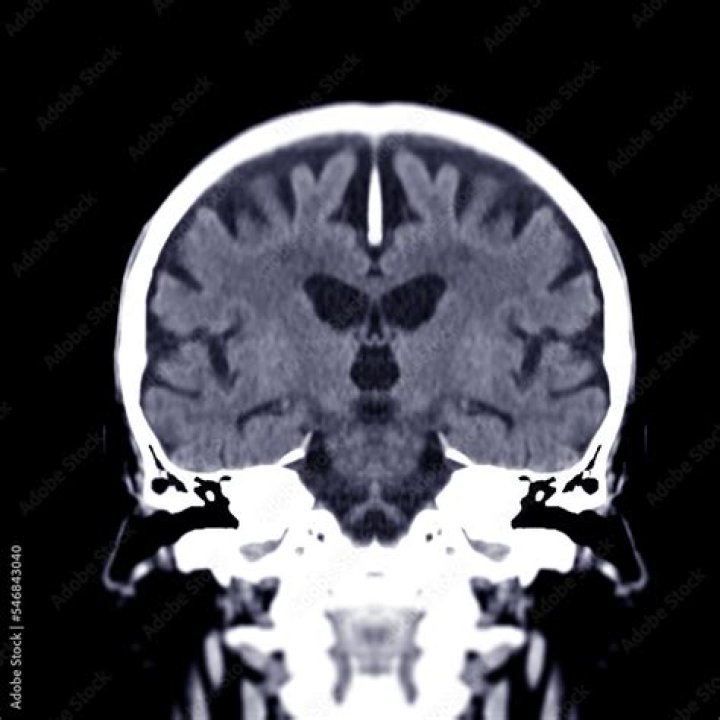

Sarah Rowe A coronal section is one that separates the brain into anterior and posterior halves. The coronal section shown in Figure 19a occurs approximately halfway between these two poles, and helps to show the placement of some of the major internal structures of the brain that will be referred to elsewhere.

A coronal plane (also known as the frontal plane) is any vertical plane that divides the body into ventral and dorsal (belly and back) sections. It is one of the three main planes of the body used to describe the location of body parts in relation to each other axis.

Coronal Plane (Frontal Plane) – A vertical plane running from side to side; divides the body or any of its parts into anterior and posterior portions.

• This type of magnetic resonance imaging (MRI) study looks at the brain with 28 coronal (vertical – side to side) cuts that begin at the back of the brain and work forward.